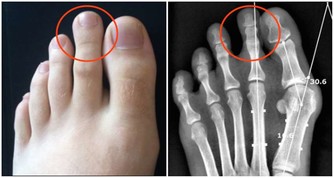

前幾天看到一個患者,三十歲左右的一個女性,她來看病時間,就是嘴周圍皮膚紅丘疹,尤其是下頜部位發病較多。她的問題比較特殊,就是找了好多地方治療,效果都不好。她吃過中藥、西藥,還用過外用藥,都不行。

來找我時候,她的下巴處可見紅丘疹,還有就是下頜部位皮膚都是紅的。問她病史,也是好一段時間壞一段時間。除此之外身體還是比較好的,沒有啥問題。我仔細望聞問切,也沒有發現任何問題。

這個患者,下頜部位出現紅丘疹過敏,就是因為氟的原因。讓她在購買牙膏時候,用不含氟的,就避免了這種問題的出現。